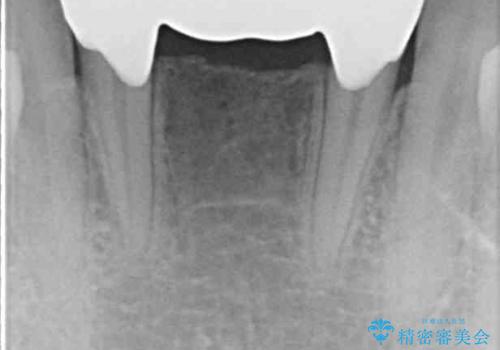

ワイヤー装置により矯正治療を行うとともに舌突出癖改善のためのトレーニングをしっかりと行っていただき、咬み合わせが安定した位置となったタイミングで下顎前歯にブリッジの仮歯を装着していく計画としました。

矯正治療終了後に速やかにオールセラミックブリッジを装着していくこととしました。